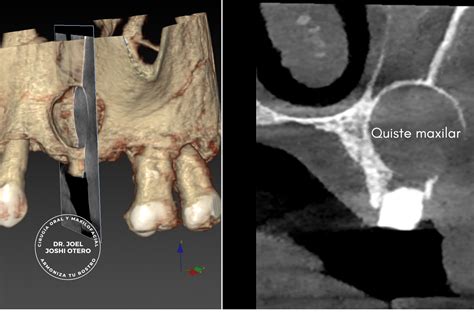

Ejemplo de quiste maxilar detectado en una radiografía.

Generalmente es necesario realizar una radiografía para diagnosticar esta patología que se manifiesta a través de una zona oscura en el hueso. En la ortopantomografía (radiografía en 2D de toda la boca) el quiste maxilar se observa como una zona oscura y redondeada en forma de bolsa.

Sin embargo, la confirmación de la presencia de un quiste radicular se obtiene mediante imágenes radiográficas como las radiografías periapicales, las ortopantomografías (visión panorámica de ambos maxilares) o las tomografías computarizada de haz cónico (CBCT).

Ofrece una visión detallada del volumen, relación con estructuras anatómicas y si hay afectación de raíces o del seno maxilar.